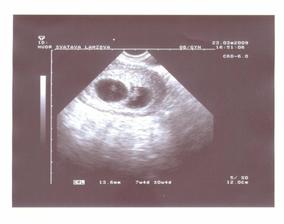

23.3. - máme průkazku!!! 🙂 kontrola u paní doktorka, podle utz jsme hodně porostli a máme i dvě srdíčka, hurááá. Dokonce to vypadá, že to budou jednovaječné dvojčátka. Vypsána nemocenská a musíme odpočívat. Jsem dost unavená a už přesně vím, co jsou to těhotenské nevolnosti, brrrrrrr. Jedno miminko je 8+0, druhé 7+4 - je menší, ale snad to dožene.